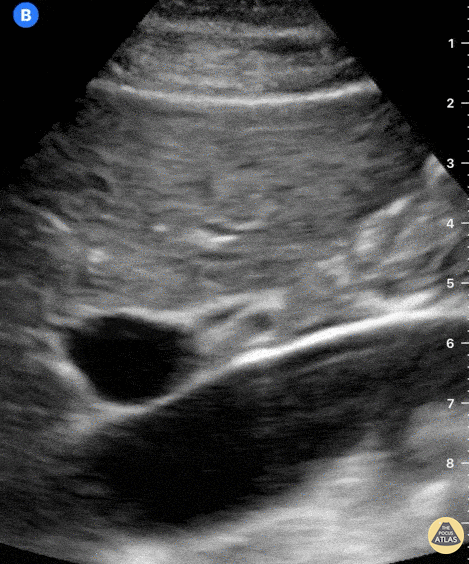

The large, pulsatile inferior vena cava lies at the bottom of the screen. Anterior to it and from left to right we see the large portal vein and small, round hepatic artery. Just above the hepatic artery lies another tubular structure which presents hyperechoic walls and an anechoic lumen; this is the common bile duct. Dr. Felipe Urriola P. Emergency Unit, Puerto Aysen Hospital. Chilean Patagonia.